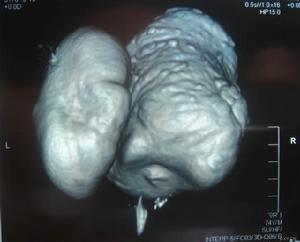

5.CT可顯示患者肝內膽管的擴張和變形。若CT顯示膽管樹不規則分支或局灶性擴張,則提示患病的可能。